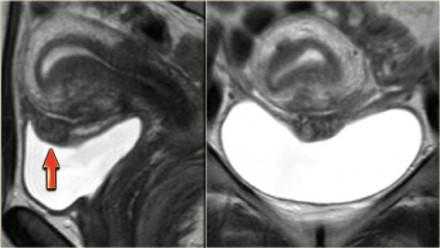

На Т2 взвешенных МР-томограммах определяются признаки эндометриоза с поражением стенки мочевого пузыря

На сагиттальных Т2 взвешенных МР-томограммах определяется поражение стенки мочевого пузыря на всю ее толщину, обусловленное эндометриозом, дающей изоинтенсивный сигнал по сравнению с мышцами; видны также гиперинтенсивные очаги, сопоставимые с расширенными эндометриальными железами. На Т1 взвешенной МР-томограмме с жироподавлением в зоне кровоизлияния визуализируются множественные мелкие кисты, дающие гиперинтенсивный сигнал